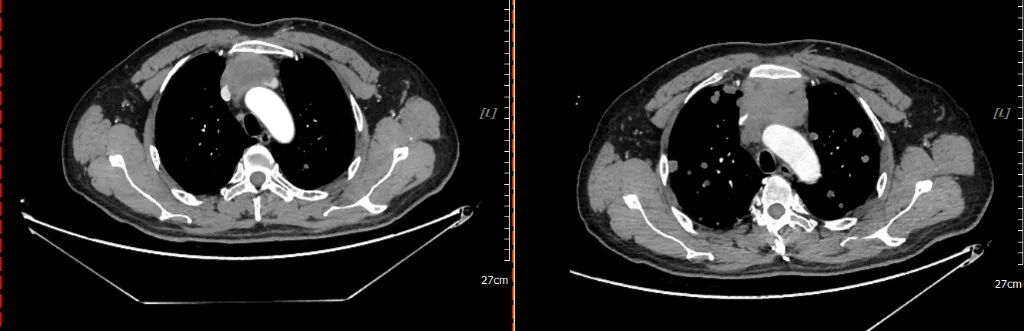

2021-02-20 2021-04-30

2周期化疗后复查疗效评价:PR

2021-04-30 2021-07-06

(四周期化疗后)复查疗效评价:SD(两肺及胸膜结节减少缩小;纵隔前间隙、纵隔内及两肺门淋巴结(2.5×3.0cm)较前部分缩小。